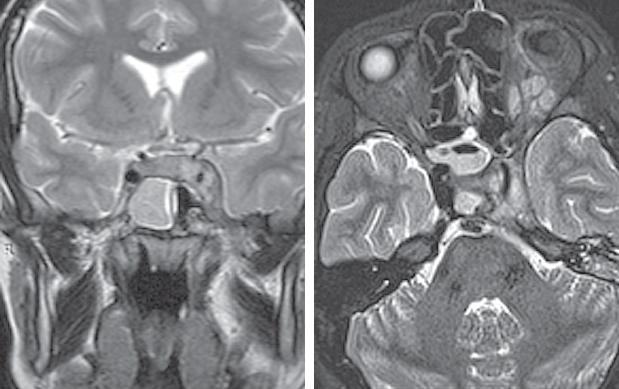

По результатам МРТ головного мозга от 16.06.2021 (рис. 2): МР-признаки подоболочечного скопления жидкости с высоким содержанием белка, воспалительных изменений оболочек в левой лобной области. Картина соответствует субдуральной эмпиеме.

Рис. 2. Магнитно-резонансная томография головного мозга от 16.06.2021: а — сагиттальная проекция в режиме Т2. Прослеживаются воспалительные изменения оболочек в левой лобной области. Картина соответствует субдуральной эмпиеме; b — аксиальная проекция в режиме Т2. Снижение пневматизации левой верхнечелюстной пазухи, пристеночный отек слизистой; c — аксиальная проекция в режиме Т2. Снижение пневматизации клеток решетчатого лабиринта; d — аксиальная проекция в режиме Т2. Воспалительные изменения оболочек в левой лобной области, субдуральная эмпиема

Fig. 2. Magnetic resonance imaging of the brain from 16.06.2021; a – sagittal projection in T2 mode. Inflammatory changes in the membranes in the left frontal region are traced. Picture consistent with subdural empyema; b – axial projection in T2 mode. Decreased pneumatization of the left maxillary sinus, parietal edema; c – axial projection in T2 mode. Decreased pneumatization of cells of the ethmoid labyrinth; d – axial projection in T2 mode. Inflammatory changes in the membranes in the left frontal region, subdural empyema

По результатам МСКТ ОНП от 16.06.2021: КТ-признаки синусита, осложненного эмпиемой левой лобной доли (рис. 3). В сравнении с данными МСКТ от 04.06.2021 отмечается положительная динамика в виде улучшения пневматизации левой лобной и верхнечелюстной пазух, а также клеток решетчатого лабиринта.

Рис. 3. Мультиспиральная компьютерная томография околоносовых пазух и головного мозга от 16.06.2021: а — аксиальная проекция в режиме brain. Отмечается увеличение пневматизации лобной пазухи; b — коронарная проекция в режиме brain. Восстановлена пневматизация клеток решетчатого лабиринта слева, сохраняется очаг поражения левой лобной доли; c — коронарная проекция в режиме brain. Восстановлена пневматизация левой верхнечелюстной пазухи; d — сагитальная проекция в режиме brain. Улучшение пневматизации левой лобной пазухи; e — аксиальная проекция в режиме skull. Улучшение пневматизации левой лобной пазухи; f — коронарная проекция в режиме skull. Восстановлена пневматизация левой верхнечелюстной пазухи; g — коронарная проекция в режиме skull. Восстановлена пневматизация левой верхнечелюстной пазухи, пристеночный отек; h — сагиттальная проекция в режиме skull. Улучшение пневматизации клеток решетчатого лабиринта, лобной пазухи

Fig. 3. Multispiral computed tomography of the paranasal sinuses and brain from 06.16.2021: a – axial projection in brain mode. There is an increase in pneumatization of the frontal sinus; b – coronary projection in brain mode. The pneumatization of the cells of the ethmoid labyrinth on the left was restored, the lesion of the left frontal lobe remains; c – coronary projection in brain mode. Restored pneumatization of the left maxillary sinus; d – sagittal projection in brain mode. Improvement of pneumatization of the left frontal sinus; e – axial projection in skull mode. Improvement of pneumatization of the left frontal sinus; f – coronal projection in skull mode. Restored pneumatization of the left maxillary sinus; g – coronal projection in skull mode. Restored pneumatization of the left maxillary sinus, parietal edema; h – sagittal projection in skull mode. Improvement of pneumatization of cells of the ethmoid labyrinth, frontal sinus